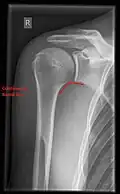

X-ray

Projectional radiography views of the shoulder include:

- AP-projection 40° posterior oblique after Grashey

The body has to be rotated about 30 to 45 degrees towards the shoulder to be imaged, and the standing or sitting patient lets the arm hang. This method reveals the joint gap and the vertical alignment towards the socket.[26]

- Transaxillary projection

The arm should be abducted 80 to 100 degrees. This method reveals:[26]

- The horizontal alignment of the humerus head in respect to the socket and the lateral clavicle in respect to the acromion

- Lesions of the anterior and posterior socket border, or of the tuberculum minus

- The eventual non-closure of the acromial apophysis

- The coraco-humeral interval

- Y-projection

The lateral contour of the shoulder should be positioned in front of the film in a way that the longitudinal axis of the scapula continues parallel to the path of the rays. This method reveals:[26]

- The horizontal centralization of the humerus head and socket

- The osseous margins of the coraco-acromial arch and hence the supraspinatus outlet canal

- The shape of the acromion

This projection has a low tolerance for errors and, accordingly, needs proper execution.[26] The Y-projection can be traced back to Wijnblath’s 1933 published cavitas-en-face projection.[27]

-

CR. shoulay film. -

Transaxillary conventional radiography -

Y-projection conventional radiography